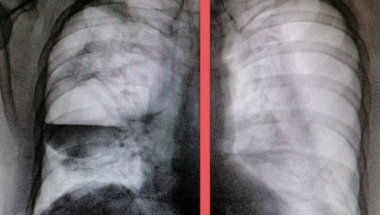

ДОКТОРКА Славица Плавшић, пулмолог у пензији, изазвала је велику пажњу на друштвеној мрежи "Твитер" пошто је на свом налогу поставила рендгенске слике плућа оболелог до корона вируса.

Фото:Твитер

Снимци плућа оболелих од ковид 19 пнеумоније нису реткост на друштвеним мрежама, али случај четрдесетогодишњака је изузетак по тежини болести и врло неуобичајеном радиолошком налазу.

- Надам се да ми нећете замерити. Снимци су узнемирујући. Трећи је нормалан снимак плућа. Прва два - обострани Пнеумоторакс, пуцање плућне марамице, гнојне шупљине у плућима, сепса, последица Ковид19. Мушкарац, 40 година. Већ три месеца се лечи у терцијарној установи. Сада је стабилан - била је њена објава на Твитеру уз приложене фотографије рендгенског снимка плућа.

- Долази до пуцања плућна марамице и са леве стране, тако да се развија обострани пнеумоторакс. То је озбиљно стање које животно угрожава пацијента. На све то створиле су се и гнојне шупљине у плућима, а затим се развила и сепса. Овакво стање, захтева хитну интервенцију грудног хирургау, што је у епидомиолошкој ситуацији тешко изводљиво - каже др Плавшић.